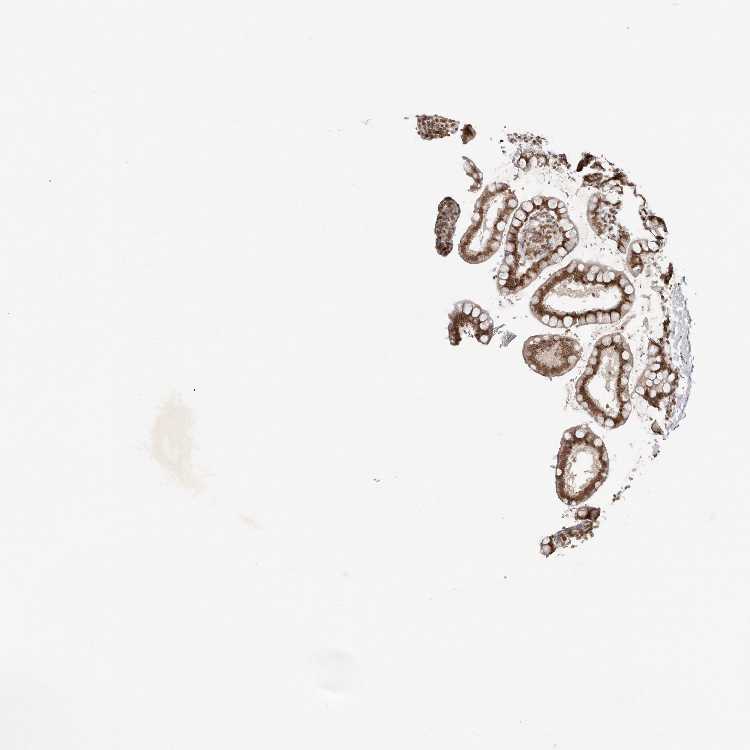

TISSUE PRIMARY DATA SMALL INTESTINE Show tissue menu

SMALL INTESTINE - Antibody stainingi

Antibody staining in the annotated cell types in the current human tissue is reported as not detected, low, medium, or high, based on conventional immunohistochemistry profiling in selected tissues. This score is based on the combination of the staining intensity and fraction of stained cells.

Each image is clickable and will lead to virtual microscopy that enables deeper exploration of all samples and also displays staining intensity scores, fraction scores and subcellular localization as well as patient and tissue information for each sample.

Antibody HPA027896Antibody HPA027897Antibody HPA027898

Glandular cells LowHighMedium